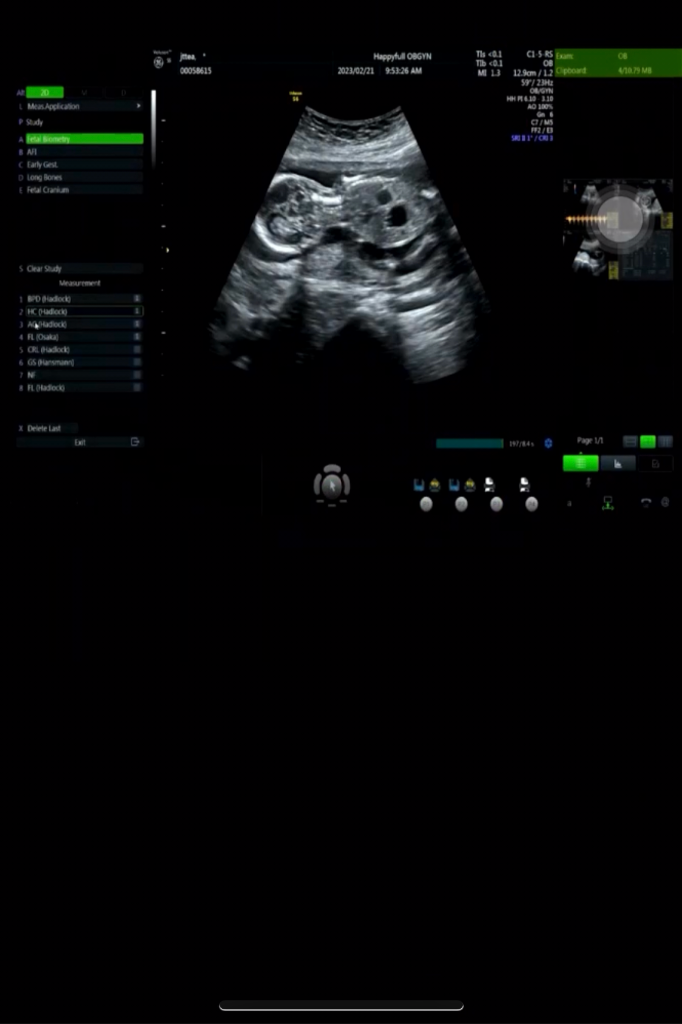

초음파에서 아기 배쪽에 검정색으로 보이는게 2개가 있는데요 이게 왜 이렇게 보이는거죠?

혹시 아기한테 문제가 되는건가요?

많이 걱정이 됩니다 산부인과선생님이 다음주에 다시 보자고했는데요 아기한테 괜찮은거겠죠?